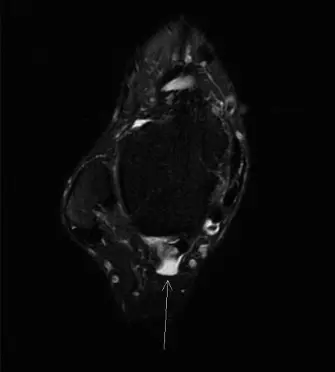

التصوير بالرنين المغناطيسي (MRI)

-

ماذا يظهر:

يُعد الرنين المغناطيسي هو الفحص الذهبي لتقييم الأنسجة الرخوة مثل الأوتار والأربطة والغضاريف. في حالة التهاب وتر قابضة إبهام القدم الطويلة، يُظهر الرنين المغناطيسي:

- التهاب الغمد الوتري: تراكم السوائل والتورم حول وتر قابضة إبهام القدم الطويلة.

- اعتلال الوتر: تغيرات في نسيج الوتر نفسه، مما يشير إلى التهاب مزمن أو تآكل.

- تضيق النفق: ضيق في النفق الليفي العظمي الذي يمر من خلاله الوتر، مما يؤدي إلى انضغاطه.

- العظم المثلث: يُظهر العظم المثلث بوضوح، مع أي تورم أو التهاب في الأنسجة المحيطة به، مما يؤكد مساهمته في الانحشار.

- استبعاد إصابات أخرى: يساعد الرنين المغناطيسي في استبعاد مشاكل أخرى مثل اعتلال وتر أخيل، أو التهاب وتر الظنبوب الخلفي، أو إصابات الأربطة.

- أهميته: يوفر الرنين المغناطيسي تفاصيل دقيقة حول مدى التهاب الوتر، وجود العظم المثلث، وتأثيره على الهياكل المجاورة، وهو أمر حاسم لتخطيط العلاج، خاصةً إذا كانت الجراحة ضرورية.

الشكل 1: صورة رنين مغناطيسي محوري لوتر قابضة إبهام القدم الطويلة ضمن نفقها الليفي العظمي. لاحظ القرب الشديد للحزمة الوعائية العصبية الظنبوبية الخلفية (إنسي لوتر FHL). توضح هذه الصورة النتائج النموذجية في أمراض وتر FHL، حيث يظهر الوتر (غالبًا مع زيادة الإشارة أو السائل المحيط به) مقيدًا بنفقه التشريحي.